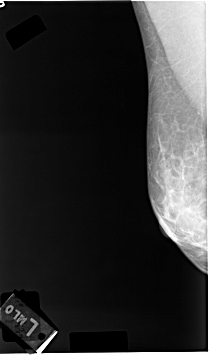

C_0039_1.RIGHT_MLO

RIGHT_CC LINES 4712 PIXELS_PER_LINE 2680 BITS_PER_PIXEL 12 RESOLUTION 50 NON_OVERLAY

RIGHT_MLO LINES 4608 PIXELS_PER_LINE 2728 BITS_PER_PIXEL 12 RESOLUTION 50 NON_OVERLAY